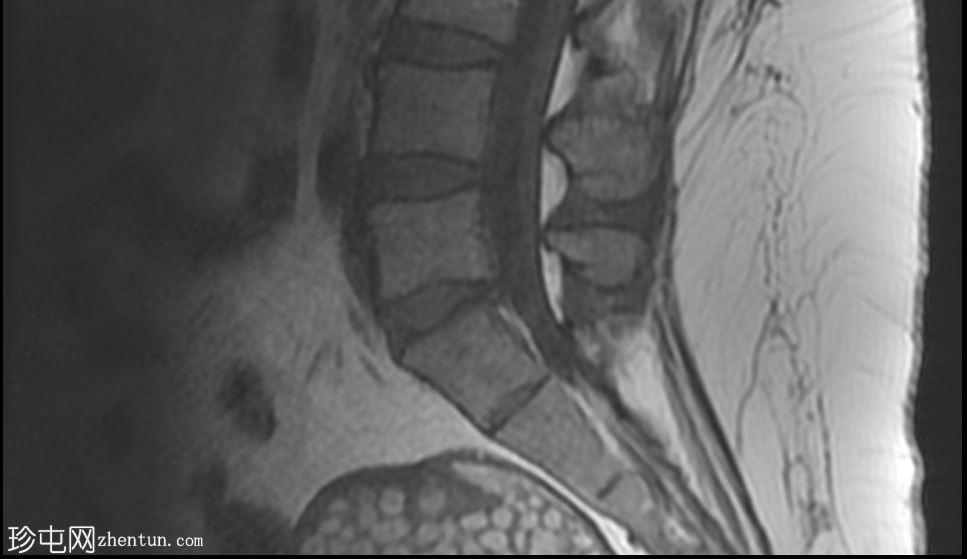

2.jpeg

矢状位

平扫

可见一主要为囊性肿块,大小为10.1 x 7.3 x 8厘米,囊内含有脂肪球。囊壁可见钙化,并对直肠乙状结肠造成压迫。